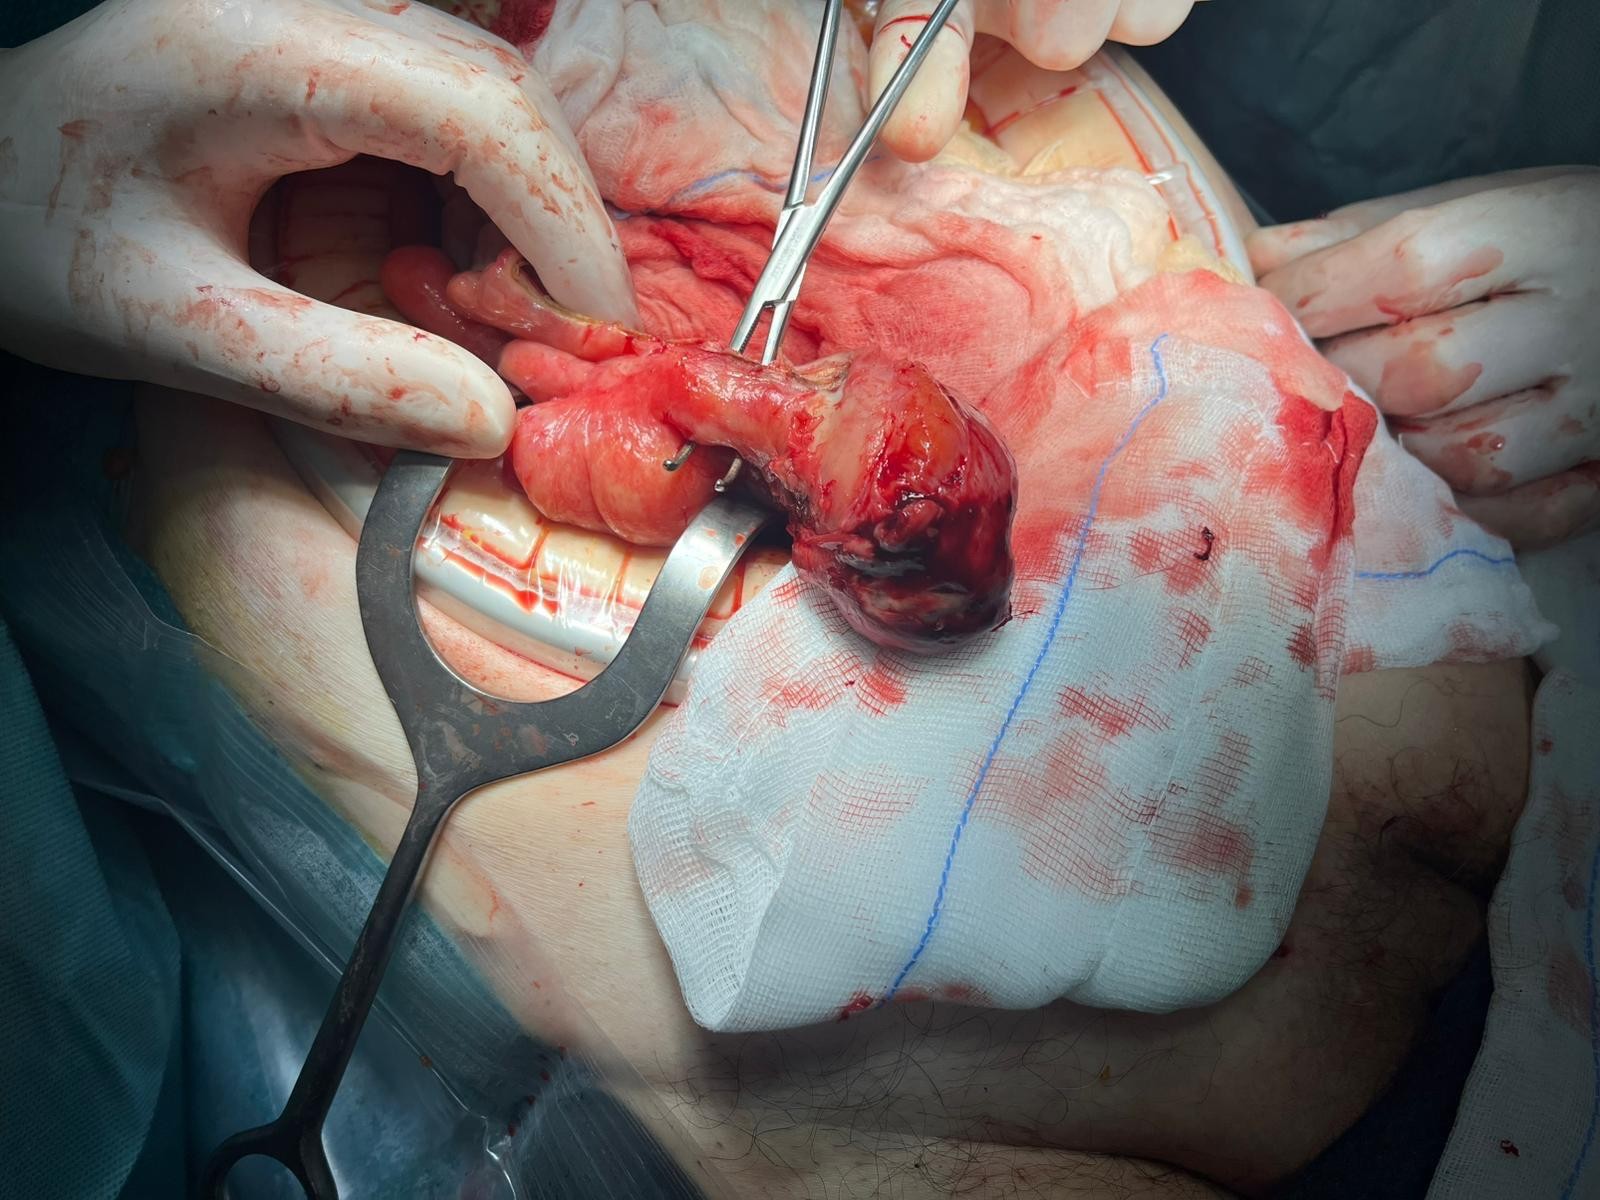

On admission, his vital signs were stable: blood pressure was 125/85 mmHg, pulse rate was 80 bpm and body temperature was 37°C. Physical examination revealed a painful, tender and irreducible right inguinal hernia without signs of peritonitis on abdominal palpation. Laboratory tests showed an elevated C-reactive protein (CRP 112.6 mg/L) as the only abnormal finding, with white blood cell (WBC) count at 2,240/µL and neutrophil percentage at 58.1%. An abdominal CT scan revealed caecal protrusion within the inguinal hernia sac, hyperaemia of the colonic wall, free fluid in the hernia sac and ascites in the peritoneal recesses (figure 1 – 3).

Figure 1: CT Scan

Figure 1